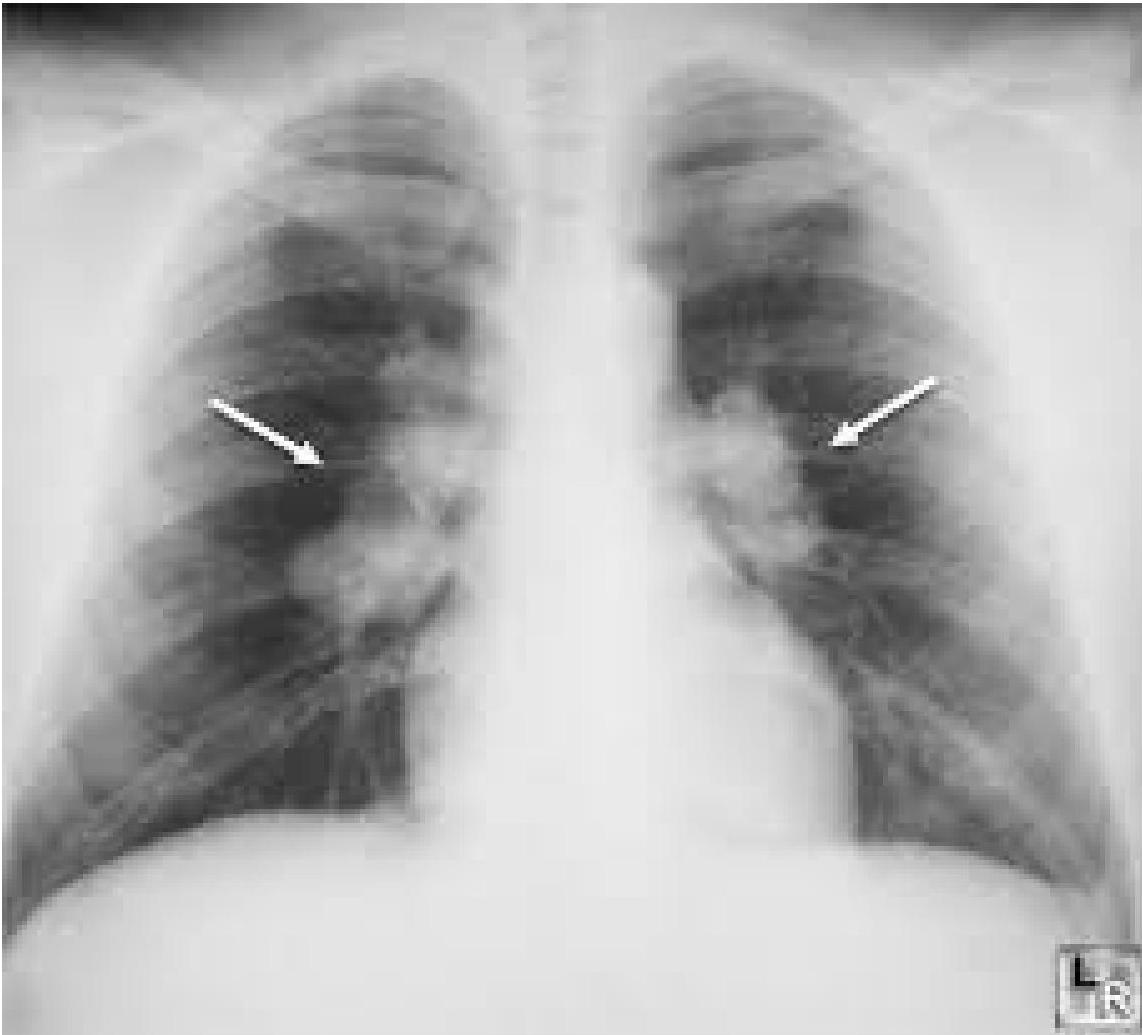

Chest X-rayx

- Bilateral hilar lymphadenopathy, interstitial changes.

Staging of Sarcoidosis on the Basis of Chest Radiographs

| STAGE | Description | Frequency |

|---|---|---|

| STAGE 0 | No abnormalities | 5%–10% |

| STAGE 1 | Lymphadenopathy (fig. A) | 50% |

| STAGE 2 | Lymphadenopathy + pulmonary infiltration (fig. B) | 25%–30% |

| STAGE 3 | Pulmonary infiltration (fig. C) | 10%–12% |

| STAGE 4 | Fibrosis | 5% (up to 25% during the course of the disease) |